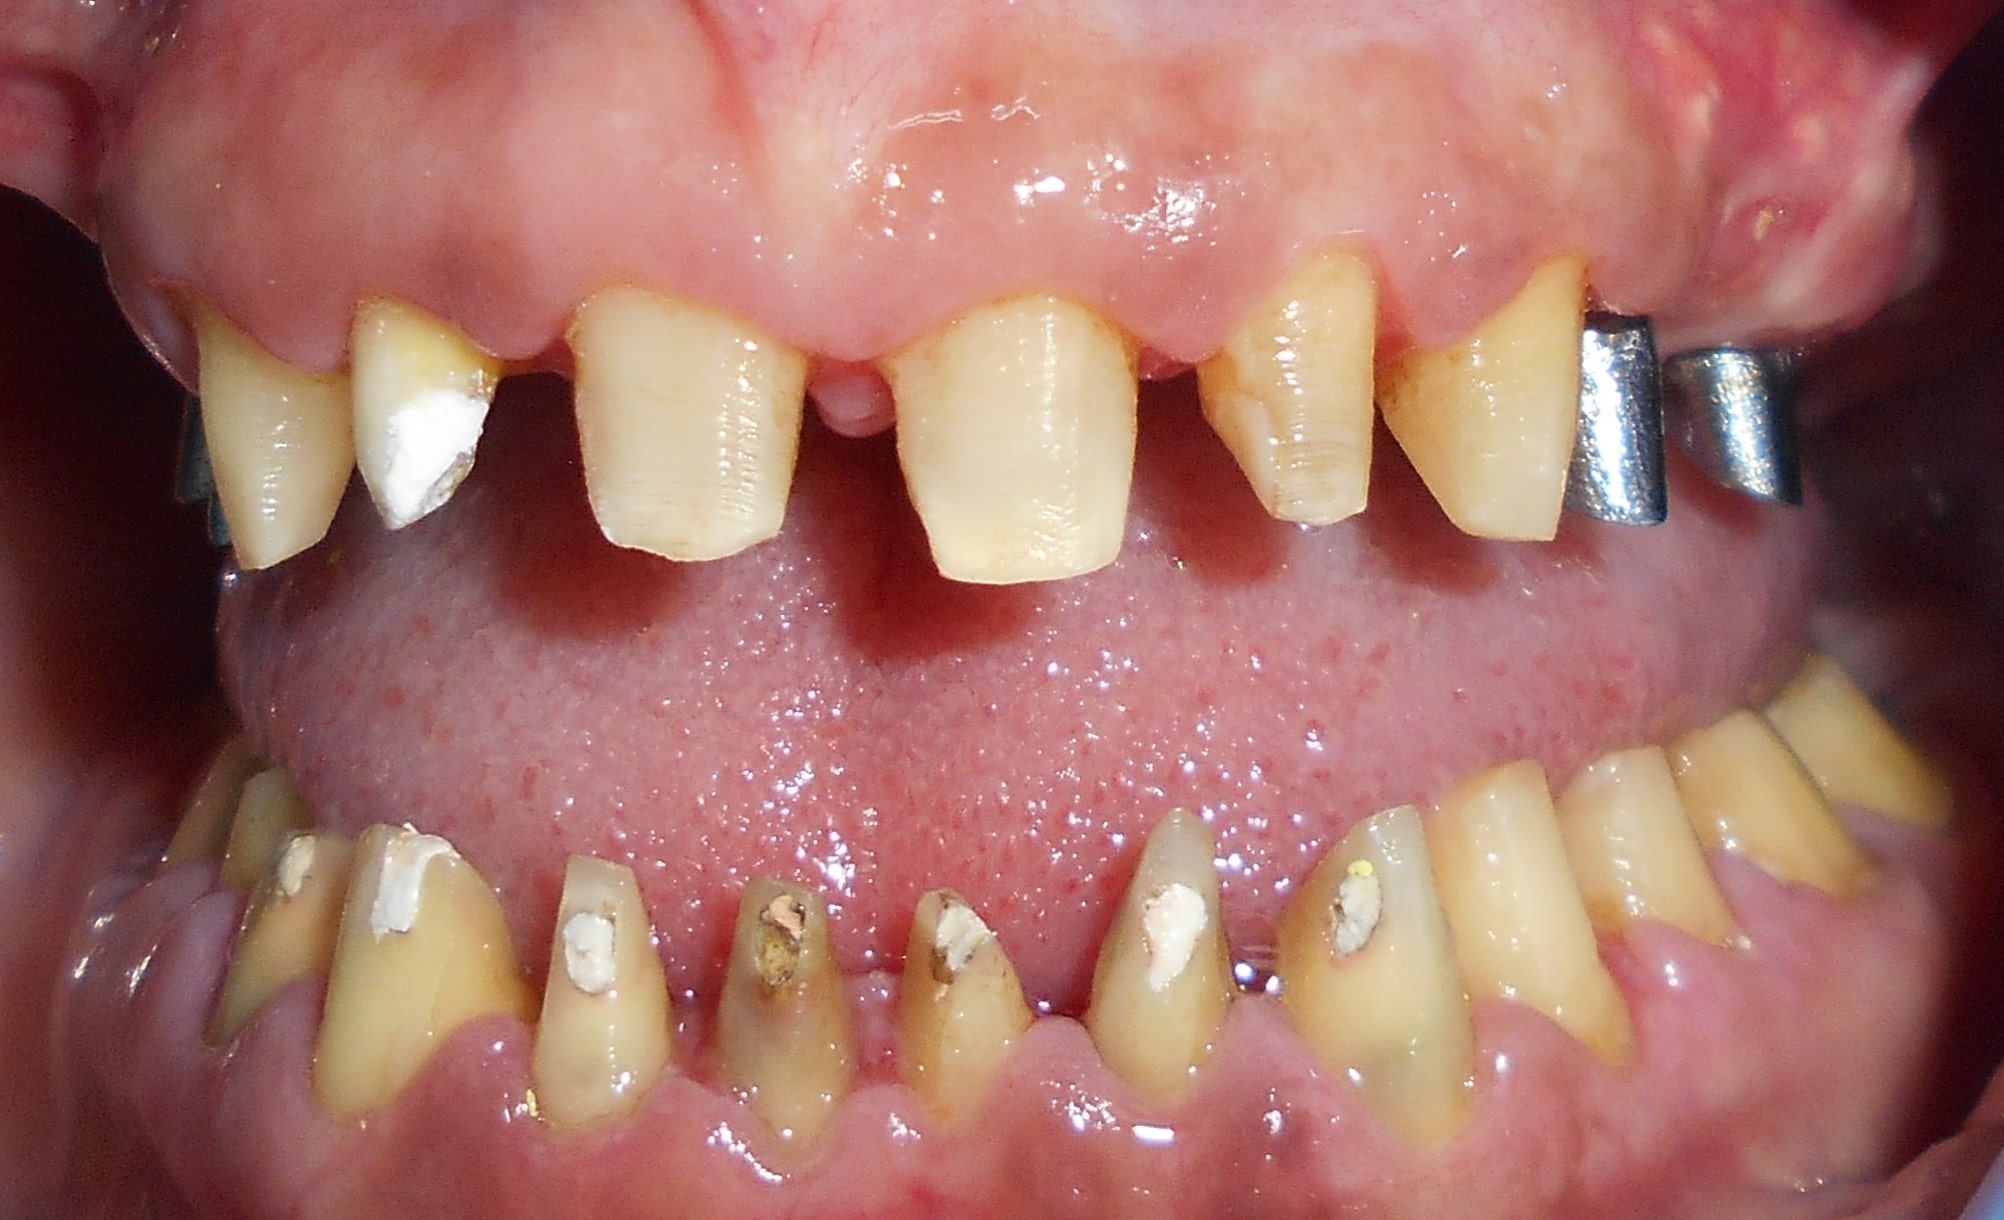

Pacijent 1

Pacijent iz Nemačke, kod koga smo estetsko i funkcionalno zbrinjavanje rešili cirkonijum keramičkim krunicama sa ugradnjom kratkih implantata u donjoj vilici zbog smanjene visine kosti, a u gornjoj vilici na levoj strani odmah nakon vađenja zuba je ugrađen standardni implantata na mesto izvađenog zuba i ugrađen je tuberopterigoidni implantat da se ne bi radila komplikovana sinus lift procedura koja bi produžila vreme završetka rada na godinu i više dana. Rad uspešno završen i pacijent nema nikakvih problema već pet godina.

Pacijent 2

Pacijent sa obe strane gornje vilice je bio bezub, sa minimalnom horizonatlnom i vertikalnom visinom kosti kao i sa spuštenim sinusom. Nakon dužeg traženja rešenja za svoj slučaj u drugim ordinacijama da bi izbegao komplikovanu sinus lift proceduru prihvatio je naš predlog da se ugrade po tri implantata sa obe strane gornje vilice od kojih su dva tuperopterigoidna implanta, koji su rešili problem spuštenog sinuasa sa minimalnom traumom prilikom ugradnje. Slučaj rađen pre četiri godine. Na poslednjoj kontroli izgleda besprekorno.

Pacijent 3

Pacijent dolazi sa starim mostovima i izraženom parodontopatijom u donjoj vilici. Urađeno je skidanje postojećih mostova i istovremena ekstrakcija svih parodontopatičhin zuba uz ugradnju sedam implantata u gornjoj vilici i pet implantata u donjoj vilici. Pacijent je nakon tri dana bio privremneo protetski zbrinut sa fiksnim privremeni krunicama koje su fiksirane na tek ugrađenim implantaima. Nakon četiri meseca je izrađen fiksni cirkonijum kermički- bezmetalni most u gornjoj i donjoj vilici. Rad uspešno završen pre tri godine.

Pacijent 4

Pacijent iz inostranstva doalzi sa totalnom protezom u gornjoj vilici i sa uznapredovalom parodontopatijom preostalih zuba u donjoj vilici. Pacijent navodi da su mu u inostranstvu rekli da je nemoguće u gornjoj vilici ugraditi implantate bez velikih hirurških zahvata koji podrazumevaju transplantaciju kosti sa udaljenih delova tela i sinus lift proceduru. U gronjoj vilici je bila minimalna količina kosti sa izraženo spuštenim sinusima i sa minimalno vretikalnom i horizontalnom visinom kosti. Naše rešenje se sastojalo u sledećem: ugradnja deset implantata u gornjoj vilici u raspoloživu kost sa ugrdnjom veće količine veštačke kosti, od deset ugrađenih implanta dva implantata su tuberopterigoidna koji su zamenili sinus lift proceduru. U gornjoj vilici smo se opredelili za ugradnju većeg broja implantata kako bi prilikom izrade fiksnog protetskog rada dobili ravnomeran prenos pritiska žvakanja na implantate. U donjoj vilici intervencija je bila istovremena i ona je podrzumevala vađenje svih preostalih zuba i ugradnju osam implantata. Kompletno zbrinjavanje koje obuhvata hiruršku i protetsku fazu je trajalo tri meseca, tokom kojih je pacijent u gornjoj vilici bio zbrinut sa privremenom totalnom protezom, a u donjoj vilici sa fiksnim privremenim zubima koji su bili fiksirani na tek ugrađenim implantatima. Definitivni protetski rad je uspešno završen sa cirkonijum keramičkim - bezmetalnim mostovim pre četiri godine.

Pacijent 5

Pacijent kod koga je rađena kombinacija rešavanja bezubih prostora sa ugradnjom implantata, a nakon tri meseca kompletno rešavanje sa cirkonijum keramičkim -bezmetalnim krunica i mostovima.